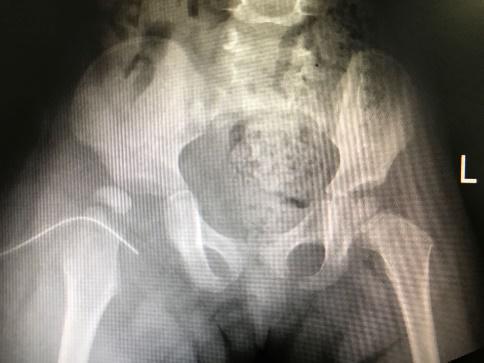

| 图 4 出现髋脱位 |

病理性髋关节脱位发生率高,达81.8%(9/11)。其中6例(54.6%)患儿入院时已有病理性髋关节脱位或半脱位情况,1例为高位脱位;3例患儿治疗过程中出现病理性髋关节脱位或半脱位。5例病髋患儿经一次手术脓肿切排冲洗引流、抗感染及人类位支具固定治疗后髋关节复位(脓肿切排时予检查髋关节复位及稳定情况从而判断是否使用支具);1例行手术切开复位后石膏固定维持复位;1例MRSA感染患儿经4次手术脓肿切排冲洗引流及支具治疗后髋关节复位;1例MSSA感染患儿入院时已有高位脱位,经清创冲洗引流后感染控制,但仍遗留高位脱位情况,以后需要进一步行重建手术治疗;1例目前有残存髋关节半脱位。36.4%放射学预后满意,63.6%(7/11)放射学预后不满意,18.2%(2/11)有残留畸形需要行重建手术。11例患儿的一般情况见表 1。病理性髋关节脱位后支具治疗见图 5。

| 图 5 治疗过程中出现髋脱位,人类位支具固定,提示复位 |